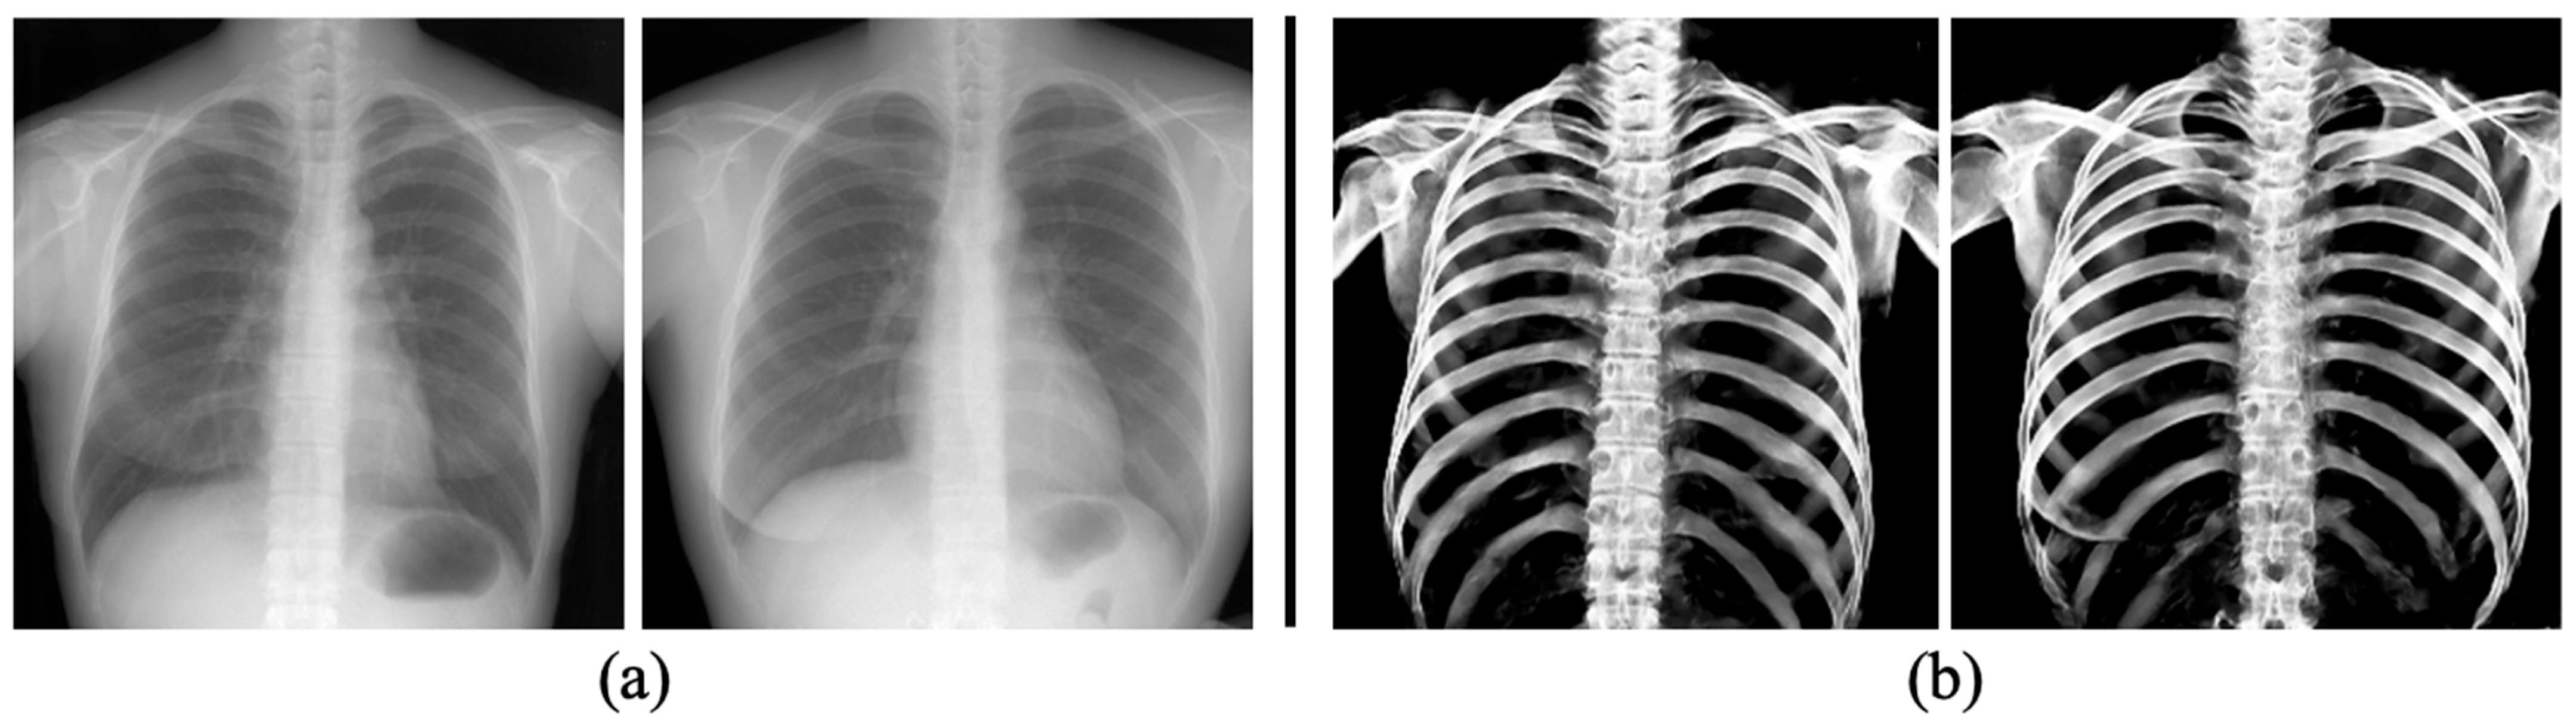

3.3. The Performance of Bone Extraction on Real 2D X-ray Images (CXRs)